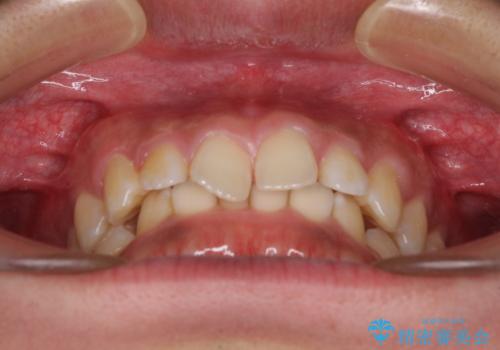

- 前歯のデコボコや隙間と深い咬み合わせ(ディープバイト)を気にして来院された患者様です。

インビザラインによる上下歯列の側方拡大と後方移動、IPR(歯と歯の間を削る)にるスペースの獲得により、デコボコとディープバイトを改善することとしました。

後方移動に際し、上下の親知らずは4本全て抜歯することとしました。

気になっていたデコボコや隙間は改善し、きれいな歯列に整えることができました。

咬合力が非常に強い方であったため、これ以上のディープバイトの改善は困難となりました。